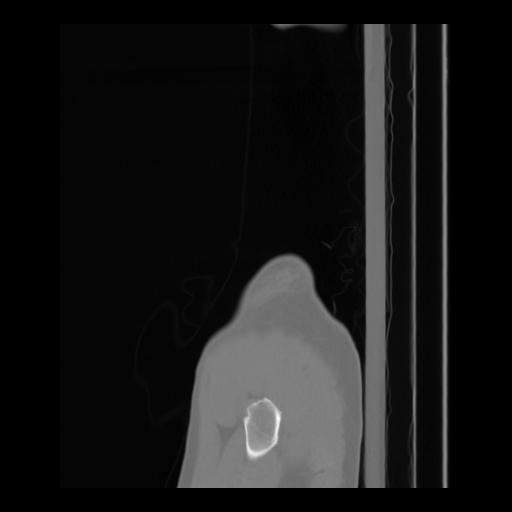

36 CUERPO,CE,Sagittal,3.000,CUERPO,Sagittal,